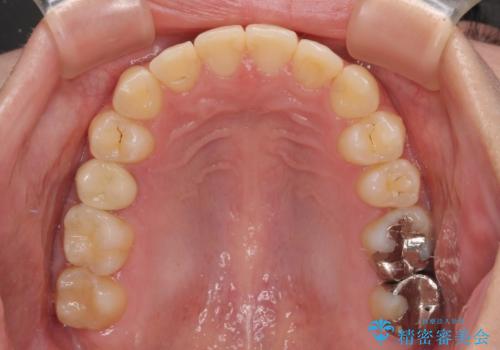

前歯のクロスバイト ギラギラのワイヤー装置で矯正治療

クロスバイトが改善する際は、前歯しか接触しないため、痛みがあったり食事が取りにくかったりと、不便な時期がありますが、1年強の短期間で無事に治療を終えることができました。